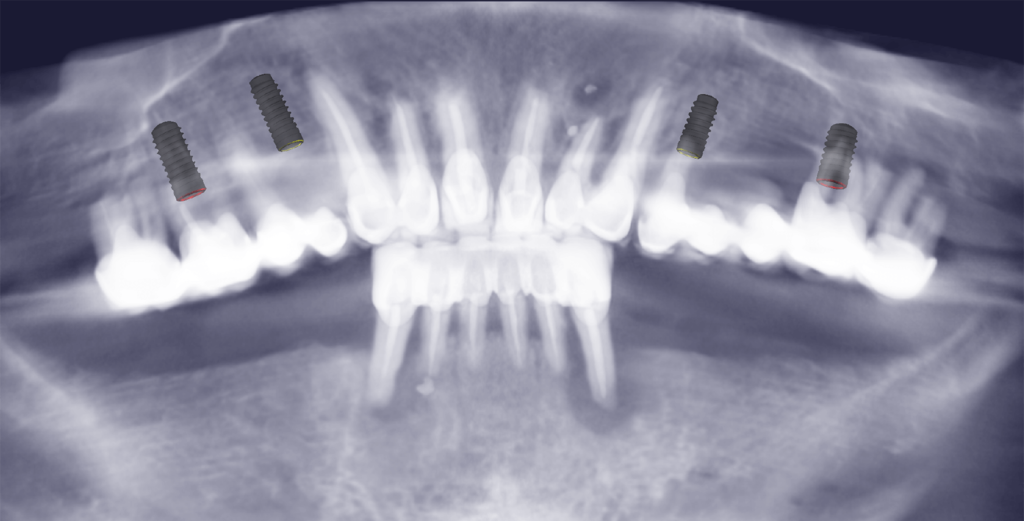

В первый визит врач провел сканирование челюстей пациента, после чего сопоставил данные КТ со сканами в программе по планированию имплантации. Разработал цифровой хирургический шаблон под имплантологическую систему Straumann и напечатал его на 3D-принтере для верхней и нижней челюстей.

За одно посещение врач удалил зубы 1.5, 1.6, 1.7, 2.4, 2.6, 2.7, 4.3, 4.2, 4.1, 3.1, 3.2, 3.3, после чего установил хирургический шаблон и 10 зубных имплантатов: 6 на нижней челюсти. Операция проходила с применением местного обезболивания и продолжалась 1,5 часа.

Через неделю пациента снова пригласили в клинику на контрольный осмотр. Дополнительно врач провел рентгенологическое исследование, на котором проследил как "села" конструкция и как спозиционировались абатменты в имплантах после нагрузки. Коррекция работы не потребовалась. После этого врач дал рекомендации по уходу, чтобы новые зубы прослужили пациенту как можно дольше: рекомендовалась профессиональная гигиена полости рта дважды в год, использование ирригатора в домашних условиях, контрольный рентген ежегодно.